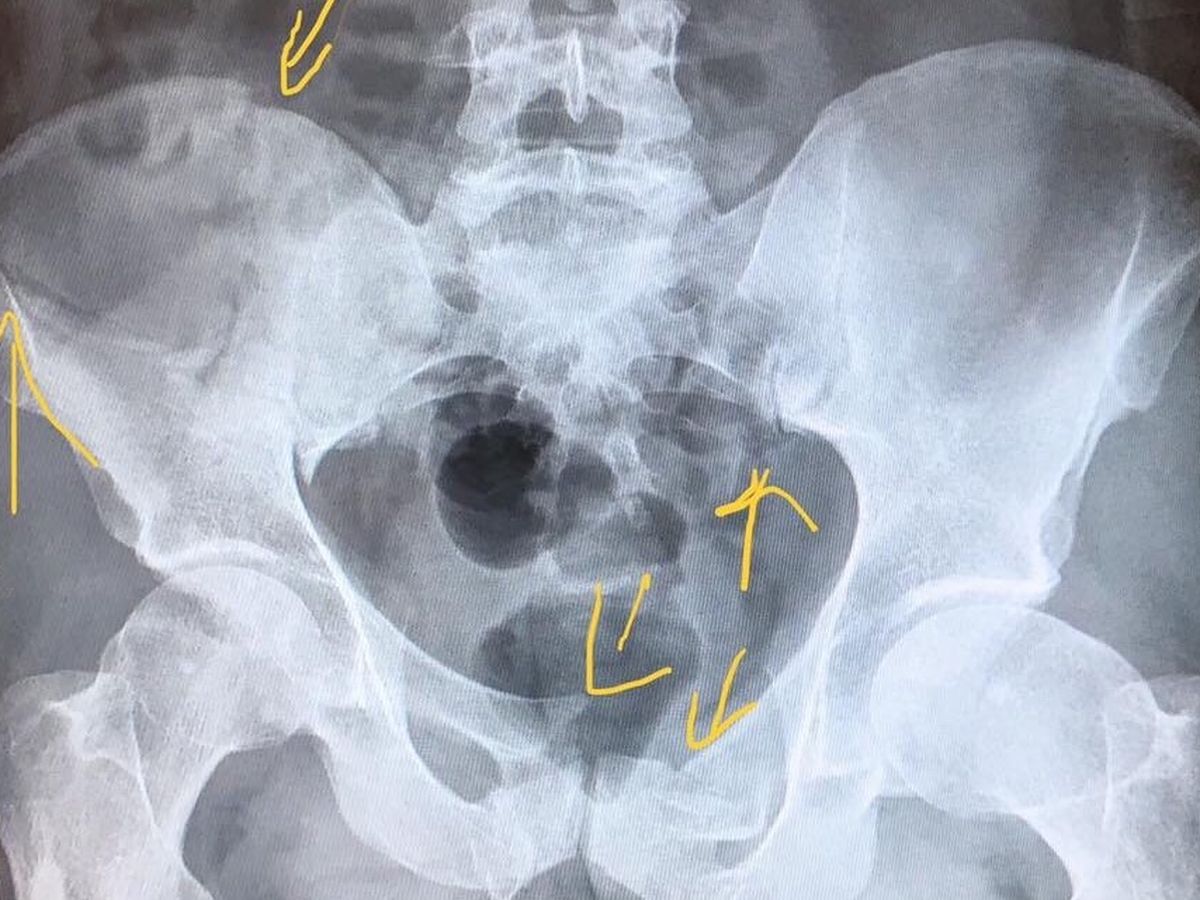

Our son, friend, co-worker, etc., Matt Thurmond, was on his way to work on his bicycle. He left his house at 3:30am on Sunday 9/16/18. Approximately 10 minutes later, he was hit by a vehicle and the driver left him laying unconscious on the side of the road. He laid there for approximately 20-25 minutes, waking up at some point, in the dark, unable to get up. He tried to flag down a couple of cars that passed by but they didn’t see him. Finally, a deputy who happened to take a wrong turn saw him and he was taken by flight for life to UMC trauma. He suffered broken facial bones around his eye and cheek, bruised lungs, broken ribs, a lacerated liver, a badly cut knee, and a broken pelvis, along with road rash all over. But he survived!! He won’t be able to work for some time and is of course amassing medical bills that he’ll have to deal with if the driver isn’t found. So he needs all the help he can get, not just for the medical, but his regular monthly bills. Those that know Matt, know he helps whomever he can. Now he needs a hand. Even if it’s just sharing this so it gets more attention, it’s greatly appreciated. Thank you in advance